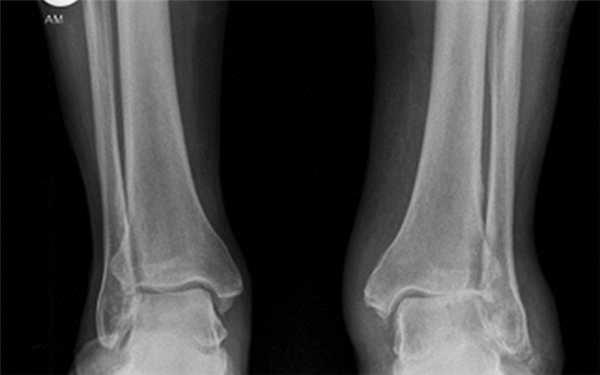

Рентгенологические стадии по Kellgren и Lawrence:

- 0 — полное отсутствие рентгенологических признаков;

- І — кистовидные изменения костной ткани, субхондральный линейный остеосклероз, краевые остеофиты небольшого размера;

- ІІ — сужение суставной щели, более выраженный остеосклероз;

- ІІІ — массивный субхондральный остеосклероз, сильное сужение суставной щели, остеофиты большого размера;

- ІV — массивные остеофиты, деформация эпифизов костей, практически полное отсутствие суставной щели.

Стадии остеоартроза голеностопного сустава